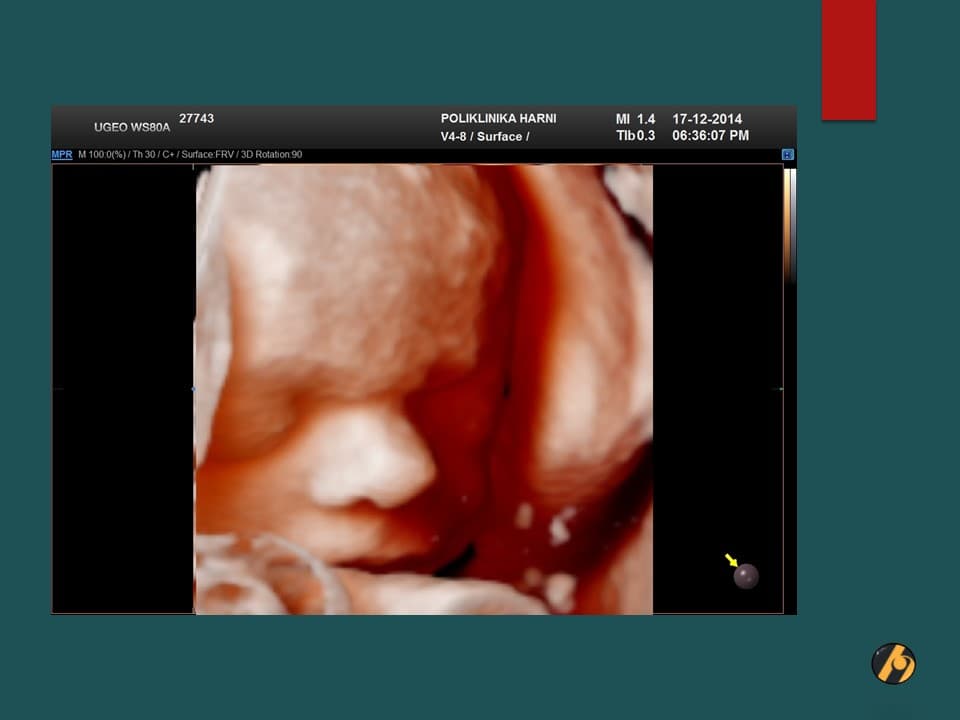

S 37. tjednom trudnoće Vaša beba postaje klinički zrela i potpuno spremna za porod. S ovim tjednom se također završava razdoblje mogućeg preranog poroda.

U sljedećim danima beba će i dalje dobivati na težini, pri čemu se ovaj dobitak osobito odnosi na odlaganje masnog tkiva. U ovo vrijeme beba odlaže u prosjeku 14 g masti/dan. Esencijalne masne kiseline ulaze i u sastav mijelina, specijaliziranog omotača moždanih i kičmenih živaca čime započinje i konačni proces dozrijevanja živčanog sustava. Ovaj proces mijelinizacije nastaviti će se i nakon bebinog rođenja.

Vaša beba dugačka je oko 47 cm, i teška 2,750 – 2,950 g.